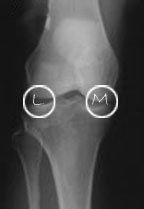

Knee surgeons refer to three main compartments within the knee - the medial compartment ('M') which is the inner side of the knee joint, the lateral compartment ('L') which is the outer side of the knee joint and the patellofemoral compartment. The latter compartment is the area between the knee-cap and the V shaped groove it sits in at the bottom of the thigh bone/femur. On the X-ray the lateral side is easy to identify because the thin fibula bone is always on the lateral side, next to the bigger shin bone (tibia).